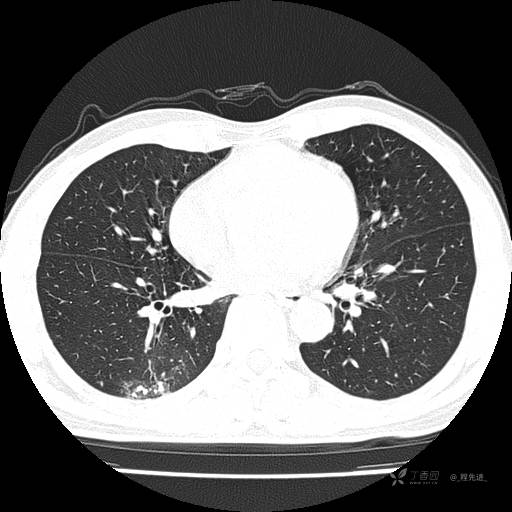

辅助检查:我院门诊胸部CT示:如下。心电图:窦性心律;正常心电图。